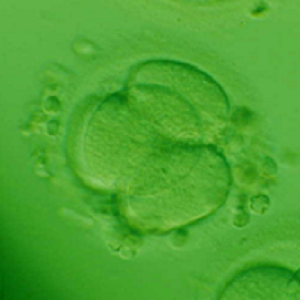

Human day 2 embryo generated in a SYNTHETIC PROTEIN-FREE (ART-7b) MEDIUM (fertilization up to day 2). Embryo transfer (n=3) was performed on day 2. The ART-7b medium has been phased out. This embryo is now a young man in his early twenties, one of a set of triplets (all boys). This was the first report of the successful generation of human embryos in a completely synthetic medium devoid of donor serum proteins. (Proc. XVI Ann. Sci Meeting Fertil Soc Australia, 2-4 Nov, 1997, Adelaide, Australia, p.34; Ali et al., Human Reprod 15:145, 2000).